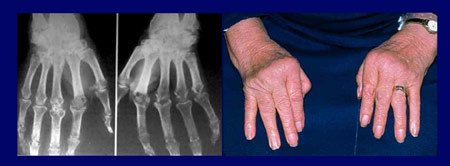

Viêm khớp dạng thấp là bệnh khớp mạn tính thường gặp nhất trong số các bệnh khớp

viêm. Tại Việt Nam, nữ giới mắc bệnh này nhiều hơn nam giới theo tỉ lệ 3/1 và

thường gặp nhất ở lứa tuổi từ 40-50 tuổi.

Tuy không trực tiếp gây tử vong nhưng VKDT khiến bệnh nhân nhanh chóng bị tàn

phế đi kèm nhiều biến chứng và giảm rõ rệt chất lượng sống.

| VKDT đặc trưng bởi các hiện tượng sưng, cứng và đau khớp |